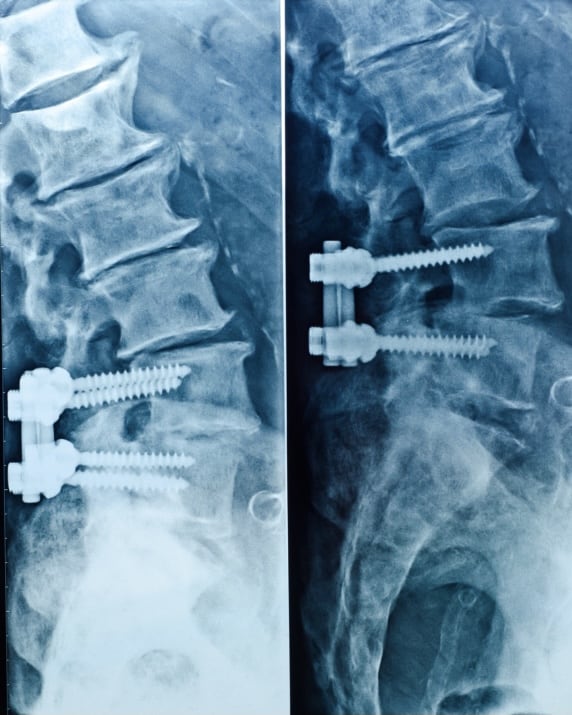

O procedimento de artrodese da coluna vertebral é utilizado em situações em que há uma deformidade ou instabilidade deste órgão. Geralmente são usados parafusos e hastes de titânio para fixação das vértebras, possibilitando a sua fusão. Pode ser indicado em várias situações, como em doenças degenerativas, hérnia de disco recidivada, tumores, trauma e infecções, como é o caso da imagem. Além disso, pode ser realizada tanto na região lombar, quanto na torácica e cervical, a depender da localização da doença.